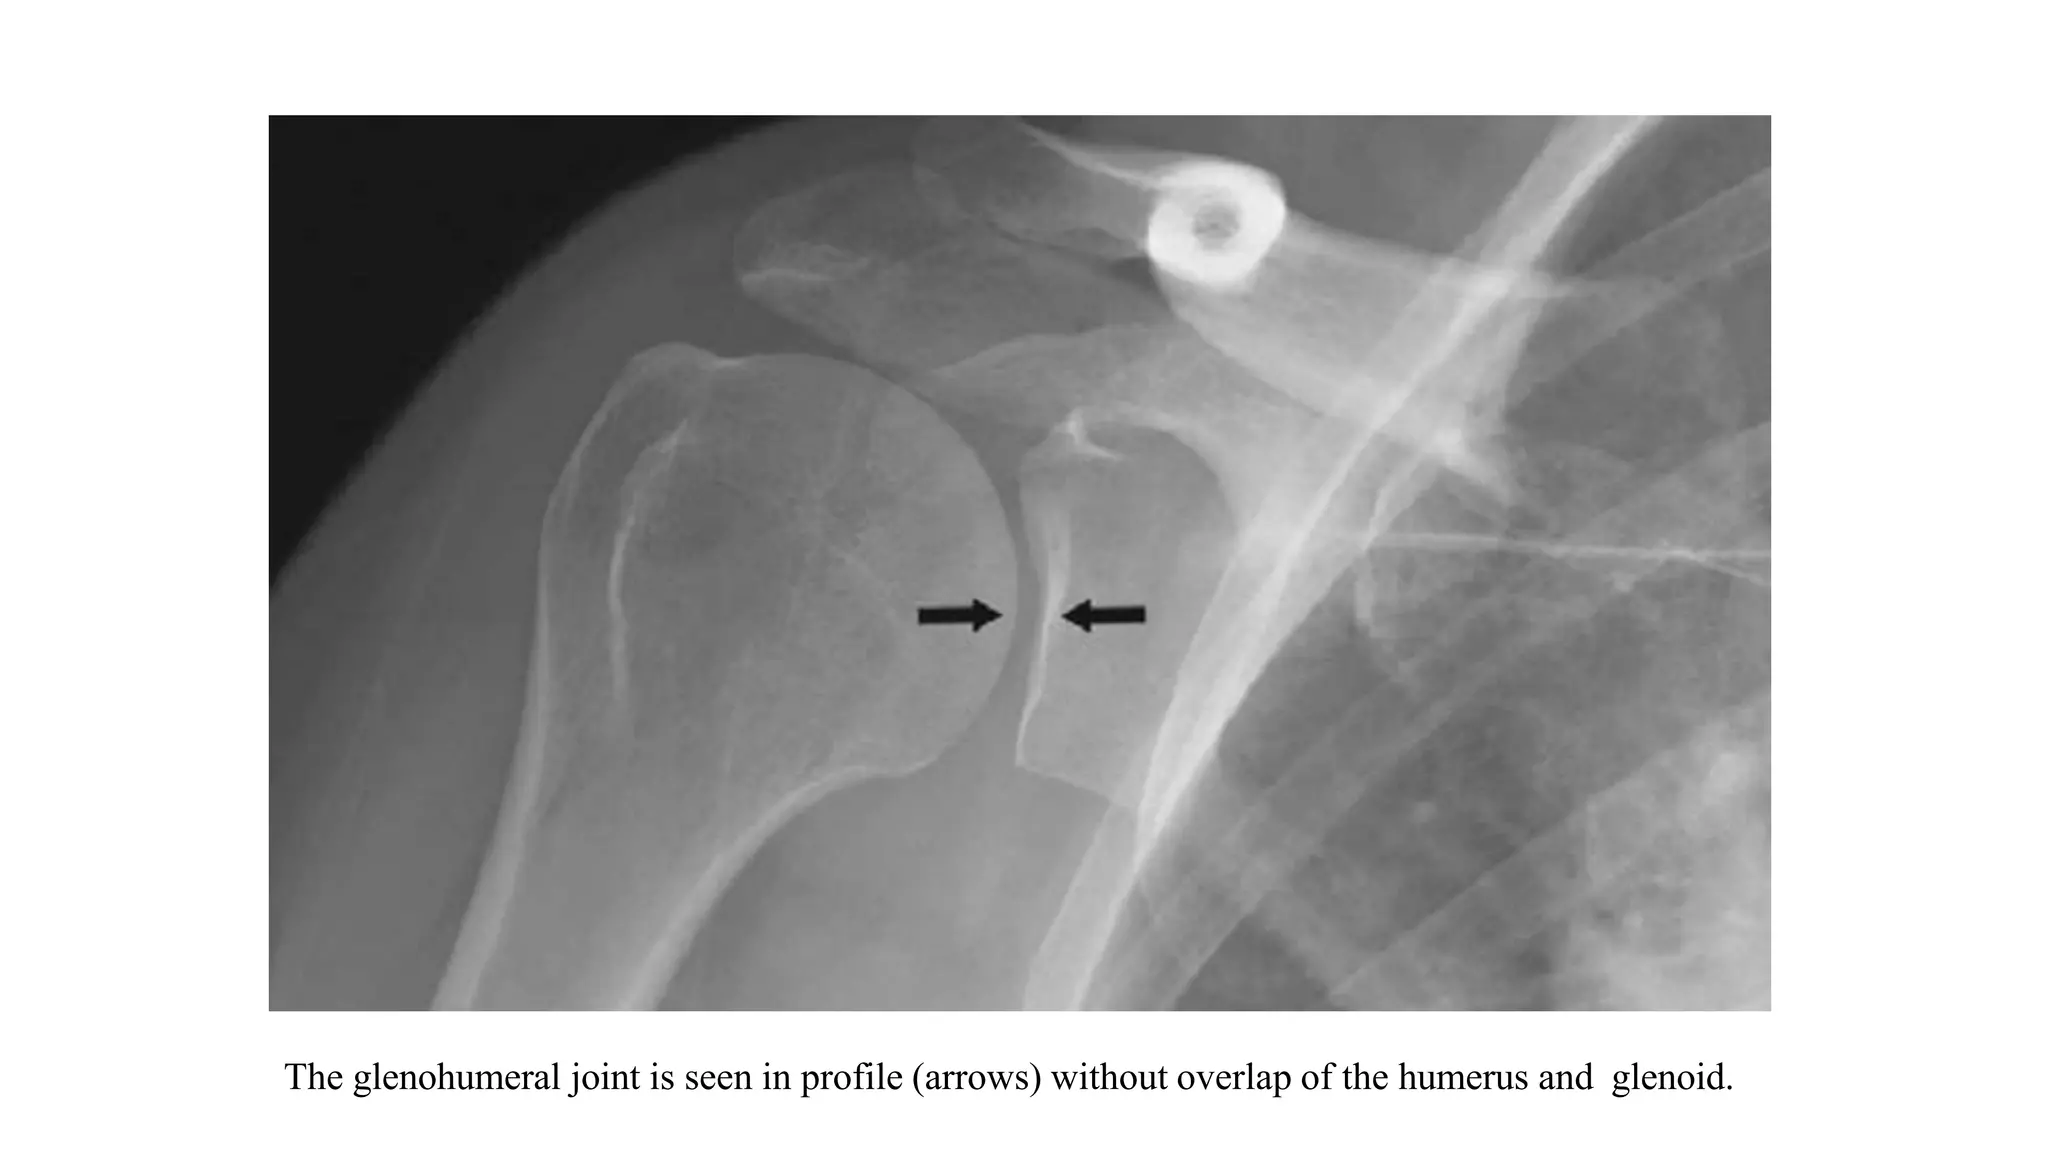

3. GRASHEY VIEW

• The Grashey view is a true anterior–posterior view of the shoulder.

• The overlap between the humerus and the glenoid seen on the AP view is removed in the Grashey projection

by rotating the patient posteriorly or angling the beam laterally.

• Helpful for: Glenohumeral Arthritis, Coracoid Process Fracture, Glenoid Fracture, Proximal Humerus Fracture.

Posterior Glenohumeral Instability.

• Evaluate: humeral head postion relative to glenoid; AC joint position/arthritis; RTC calcifications, acromial

spurring

• Acromiohumeral interval: normal = 7-14mm. <7mm indicates Massive RTC Tear. May appear falsely decreased

with posterior subluxation of the humeral head.

Position: Patient erect, turned 30-35° toward the side being xrayed

Tube: Perpendicular to plate

The glenohumeral joint is seen in profile (arrows) without overlap of the humerus and glenoid.